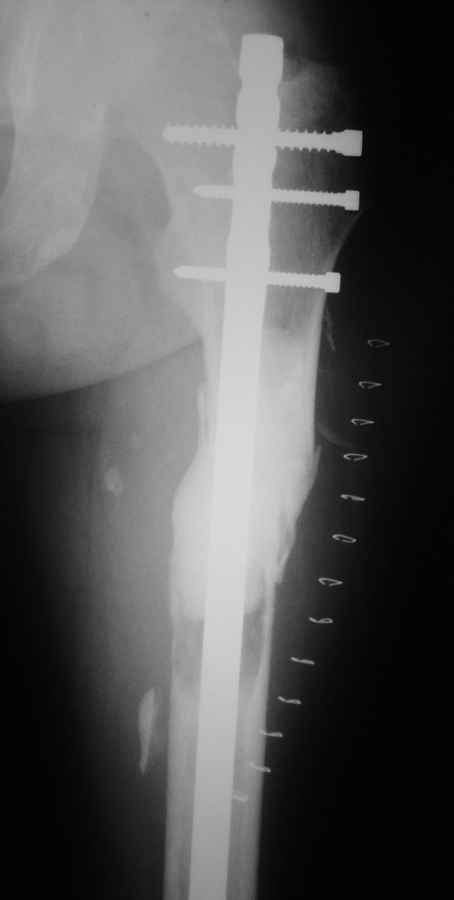

Re: Патологический перелом бедра

Добрый день. Подобное наблюдение было у меня. Надежная операция, довольный больной.